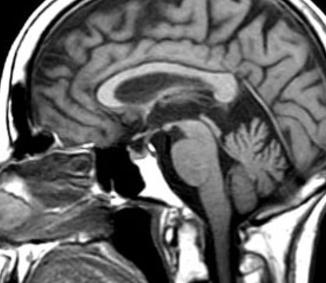

MRI normal brain -   At 6 o'clock on the image, round topped vertical white bone (dens-C2)         is below a large white almost triangular pointy bone (clivus). Brain stem (grey oval) is behind strip of black (spinal fluid - CSF). Brain stem controls everything that keeps you alive.

Cerebellar tonsil is the olive shaped grey tissue directly behind the spinal cord at the base of the occiput.